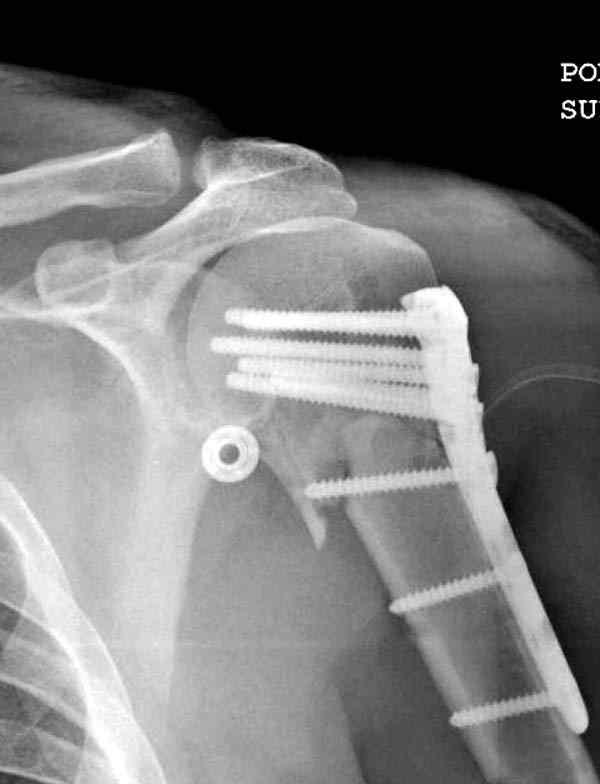

Здесь пример открытой репозиции 57 летнего с переломом плеча (1,2) смещение обнаружено на интероперационном снимке. При нормальной прямой проекция (3) угловое смещение обнаружили в аксиальной проекции (4)

После устранения смещения пластина установлена выше (5,6,7) и финальные снимки (8,9,10)

Подбор импланта тоже имеет значение, например многие импланты направлены для фиксации перелома без учета ротаторной манжетки. Предпочтительными являются низко сидящие полиаксиальные пластины, где верхние шурупы можно проводить под углом в 120 градусов. (11)